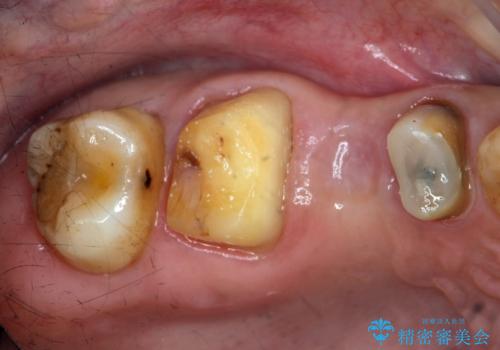

- 他院でブリッジの仮歯を入れたが、外れやすいため転院を希望された患者様です。

支台歯の形が角度が大きくついた形に形成してあり、外れやすい形になっていたため修正してから歯型をとりました。